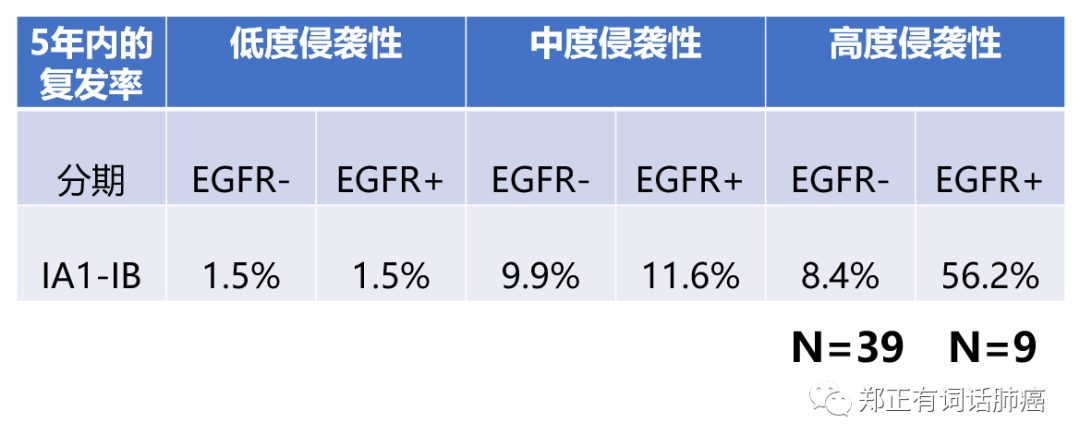

而将突变状态/分期情况以及病理亚型杂糅一起进行分析后,我们可以得到以下表格:

第二,就是该研究中在I期患者,绝大多数都是中/低度侵袭的,而表现为高度侵袭的患者并不多,其中,EGFR阴性39例,EGFR阳性只有9例。

因此,我个人的观点是,尽管EGFR突变可能在I期高侵袭人群带来不良的预后影响,但应该不至于引起高达56.2%的5年复发率。

毕竟样本量还是太小了。